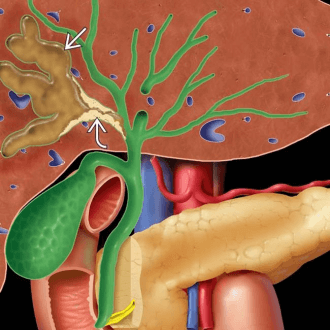

В рамках диагностики холангита также могут проводиться инструментальные исследования, такие как УЗИ органов брюшной полости, магнитно-резонансная холангиопанкреатография (визуализация желчного пузыря, желчных протоков, печени, поджелудочной железы), эндоскопическая ретроградная холангиопанкреатография, эзофагогастродуоденоскопия (осмотр органов пищеварительной системы при помощи зонда гастроскопа) и др. Методы визуализации позволяют выявить расширения и сужения желчных протоков, установить размеры органов гепатобилиарной системы и получить другие важные диагностические данные. При подозрении на холангит может быть назначена биопсия печени.

О заболевании

- УЗИ. При ультразвуковой диагностике исследуют брюшную полость, желчные пути, печень. Исследование направлено на выявление патологических расширений желчных протоков, очаговых и структурных изменений печени.

- Лучевая диагностика. Включает панкреатохолангиографию – эндоскопическую ретроградную и магнитно-резонансную, ЧЧХГ (чрескожную чреспеченочную холангиографию) с применением контраста. Эти методы исследования помогают визуализировать желчевыводящие пути, увидеть очаг патологии и понять ее причину.